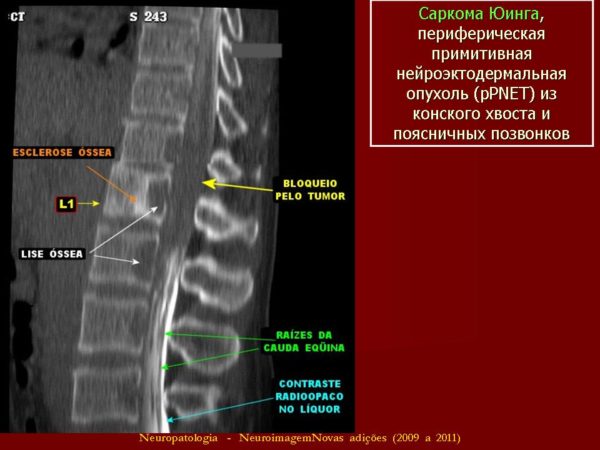

- Саркома Юинга. Встречается у детей и в молодом возрасте. Происхождение неизвестно.

- саркома Юинга диагностируется в детском возрасте и поражает структуры спинного мозга.

Саркома Юинга

Саркома Юинга – детское онкозаболевание, которое появляется в позвонках и мягких тканях позвоночника, при этом характеризуется наивысшей степенью агрессивности и быстрым метастазированием в лимфатические структуры, различные отделы скелета и легкие. Может образоваться по причине опухоли гематома позвоночника, лечение это опасное явление еще больше усложнит и усугубит самочувствие в разы.

ЗН могут быть интрамедуллярными, а именно, те, которые расположены непосредственно в спинном мозге (определяются крайне редко). Например, примитивная нейроэктодермальная опухоль, развивающаяся из нейральных клеток-предшественников. Ввиду специфичной локализации при интрамедуллярных формах оперативное вмешательство по удалению видоизмененного участка ткани произвести невозможно.